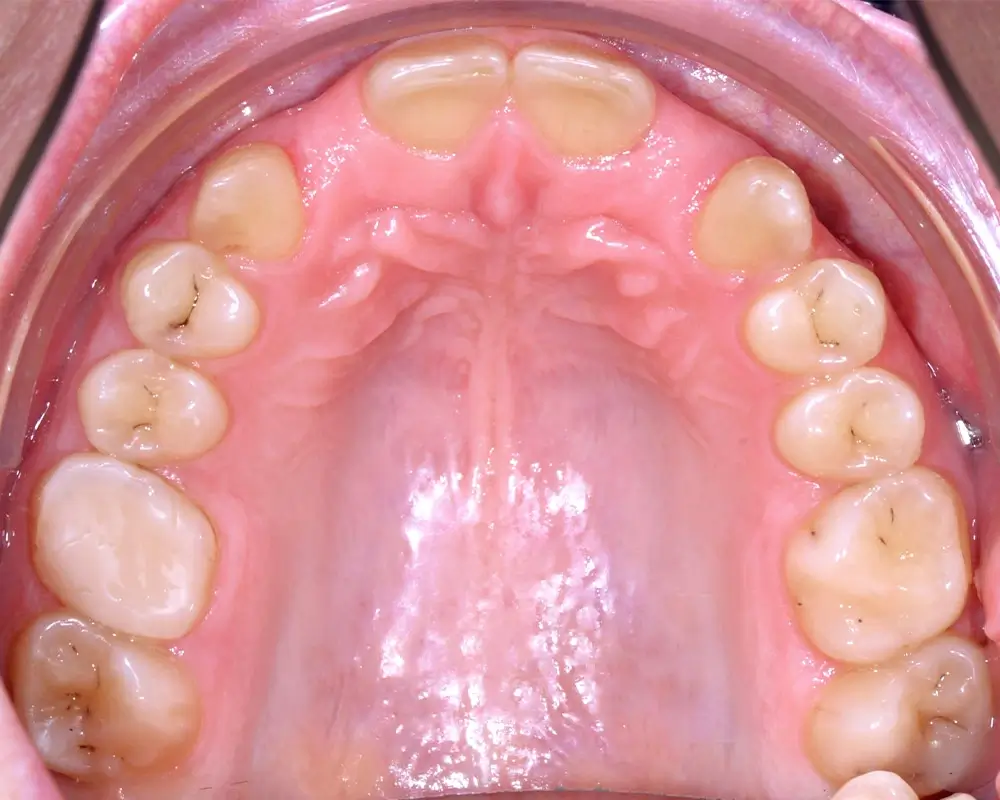

Кейс 8

Бажанова Ольга Валерьевна

Количество кап ВЧ 24

Количество кап НЧ 24

ДО